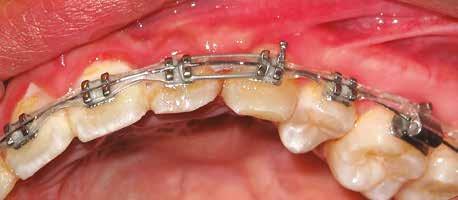

A 10 éves férfi páciens a felső frontfogai késői/nem megvalósuló előtörése miatt kereste fel a rendelőnket. A klinikai és a radiológiai vizsgálat során a jobb felső nagymetszőfog impakcióját észleltük (1. ábra). A fog horizontális tengelyállással és dilacerált gyökérrel rendelkezett. A felső dentális középvonal a fogak vándorlása miatt jelentős mértékben elcsúszott. A bal felső kismetszőfog is rendkívül kedvezőtlen pozícióba került.

A kezelés első lépéseként az összes maradó fogra breketteket rögzítettünk. A felső fogív nivellálása, a ferde tengelyállá-

Dr. Kazem Dalaie, dr. Samin Ghaffari, dr. Mazir Mir (Irán, Németország) 1. a ábra: Az intraorális felvételen jól látható a jobb felső nagymetszőfog lehetséges impakciójára utaló foghiány.

sok korrigálása, valamint az impaktálódott fog előtöréséhez szükséges hely megteremtését követően, egy merev acél ív segítségével stabilizáltuk a fogakat. Ezt követően elvégeztük a jobb felső nagymetszőfog sebészi feltárását. A fog koronáját csupán lágyrész borította, ezért nem volt szükség a csontállomány elvételére. A felszabadítás során egy 975

nm-es hullámhosszon pulzáló üzemmódban alkalmazott lézert használtunk (LaserHF standard, Hager & Werken). A teljesítménye 3 W, az aktív ciklus-idő 50%-os, a vezetőszál átmérője pedig 0,4 mm volt (2. ábra). A lézert 150 másodpercen keresztül alkalmaztuk. A fogat borító lágyrészek eltávolítását követően egy láncos brekettet rögzítettünk a metszőfog bukkális felszínére. A műtétet követően nem tapasztaltunk vérzést, nem alakult ki oedema, valamint a páciens sem számolt be fájdalom vagy bármely egyéb kellemetlenség fennállásáról. A felszabadítást követően a páciens minden hónapban háromszor jelent meg a felszabadított területre ránövő lágyrészek és az íny lézeres eltávolítása céljából. A beavatkozások során ugyanazt a lézer készüléket használtuk, mint amivel a felszabadítást végeztük. Közvetlenül a felszabadítást követően megkezdtük a fog finom extrudálását a láncos breketthez kötött füzérgumi segítségével.